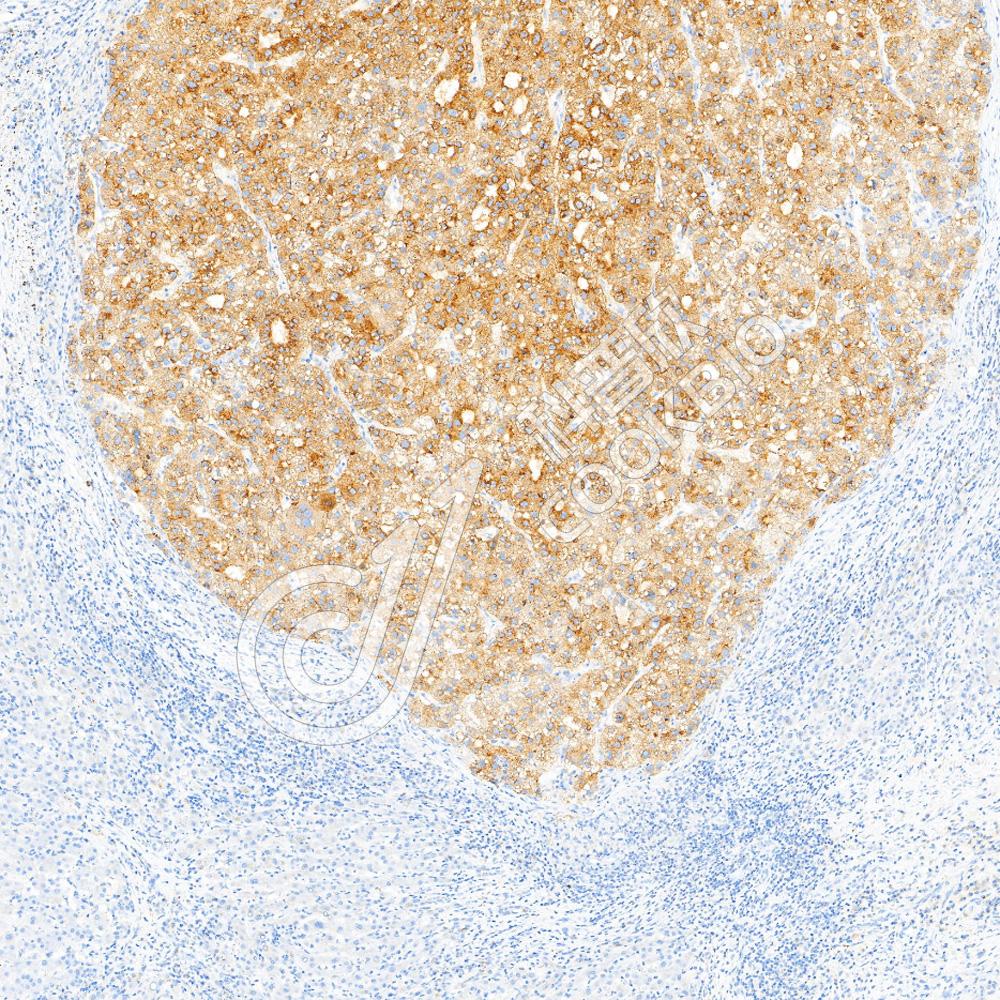

IHC检测Glypican 3蛋白(货号 K5466587).

样品: 人肝癌, 4%多聚甲醛 (货号KSG1101) 固定12-24小时.

抗原修复: Tris-EDTA抗原修复液(pH 9.0) (货号KSG1203), 水浴100℃, 25分钟.

—抗: 1: 800稀释, 4℃ 孵育过夜.

二抗: S-vision免疫组化多聚二抗(山羊抗小鼠), 即用型(货号KB3903), 室温孵育20分钟.